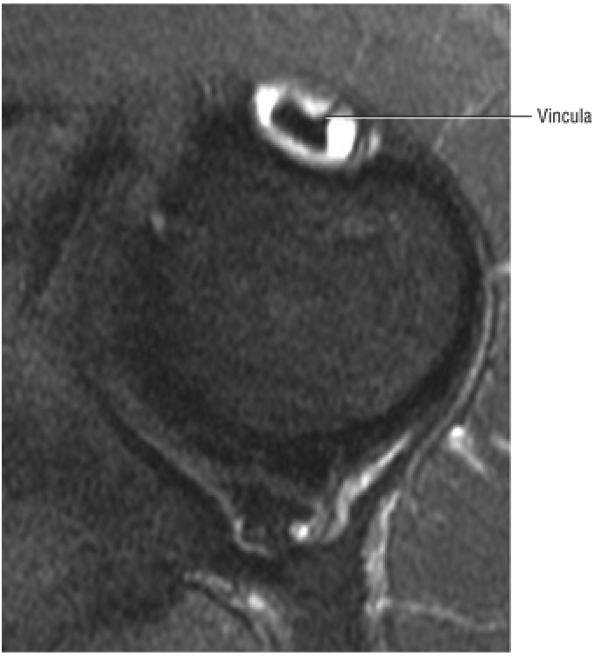

FIGURE 8.69 ● Vincula biceps extending anterior to the biceps tendon. Axial FS PD FSE image.

|